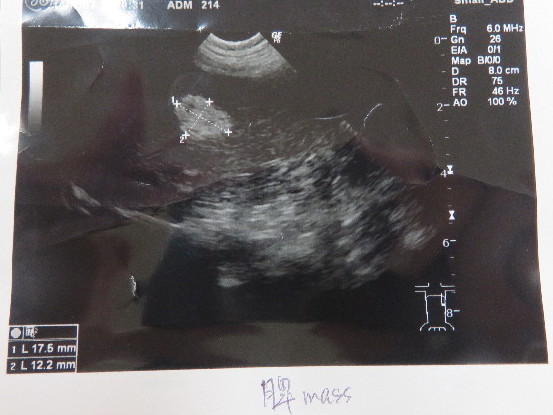

●エコー

○脾臓のmassは大きさ変わらず。

院長は『石灰化』とおっしゃっていましたよ。

前回はmassに血管も少し写りましたが(下の脾臓の血管が透けたのでしょうとのこと)、今日は全くみあたりませんでした。

massが少し厚くなったのか? もともと血管なんてまったくないかのどちらかね。